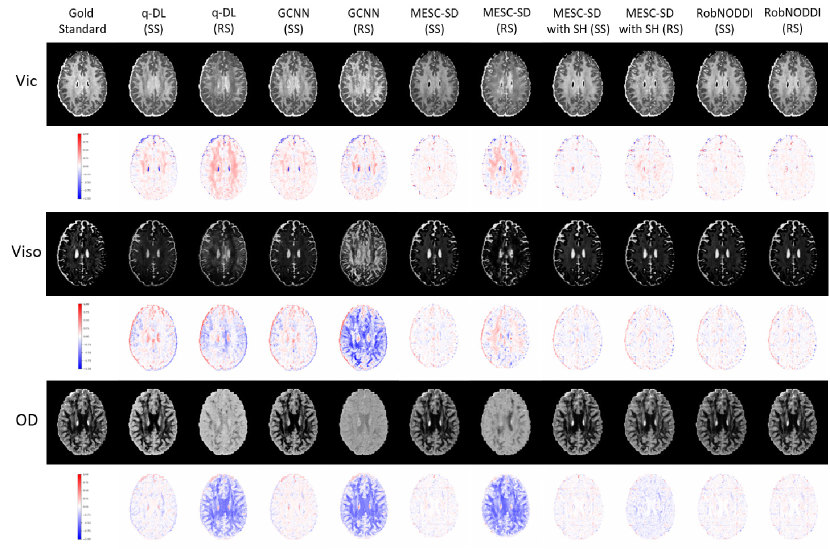

Table 1 shows the quantitative metrics of three deep learning methods under SS and RS testing. It can be observed that the existing deep learning methods suffer a significant performance drop when the diffusion direction changes, making it difficult to estimate the parameters accurately. The visual comparison in Figure 2 also demonstrates that the existing deep learning methods exhibit a clear performance degradation when the testing diffusion direction is altered. In other words, most existing deep learning methods have poor generalization to changes in dMRI diffusion direction.

Refer to caption

Figure 2: Qualitative comparison of NODDI parameter for SS and RS testing using different methods with 30 diffusion directions per shell (1000, 2000 s/mm²)

The input for training here is the SH coefficient of 30 diffusion directions with fixed uniform sampling per shell. The test is also divided into two types: SS and RS. The results are shown in Figure 2 and Table 1 corresponding to MESC-SD with SH (SS) and MESC-SD with SH (RS). It can be seen that using SH as input to estimate microstructure parameters is effective, and the results are very close to using DWI as input. When the test direction is RS, the performance also decreases; however, compared to the original MESC-SD, the RS test shows much better results. This indicates that using continuous representation of DWI as input improves the model’s generalization performance in dMRI microstructure parameter estimation, yet it still lags behind the SS test. Specifically, for Vic and OD, the visual results and error maps in Figure 2 still show some discrepancy compared to the SS testing results.

3.3.3 SS and RS test of the proposed RobNODDI method.

This part introduces our proposed RobNODDI method. As shown in Figure 1, our input is the DWI patch, and we incorporate adaptive sampling and SH coefficient fitting into the network training. During testing, we also conducted SS and RS evaluations for RobNODDI, where the SS testing uses the same sampling scheme as the comparative methods. The corresponding results are shown in Figure 2 and Table 1. It can be observed that when the testing direction changes, the results estimated by our method remain highly consistent, with almost no visible differences, and the quantitative metrics are very close as well. Compared to the original MESC-SD method, our approach achieves significantly improved generalization. Moreover, compared to MESC-SD with SH, the proposed method further enhances both performance and generalization. Therefore, our method not only achieves more accurate parameter estimation, but also demonstrates strong generalization and robustness.